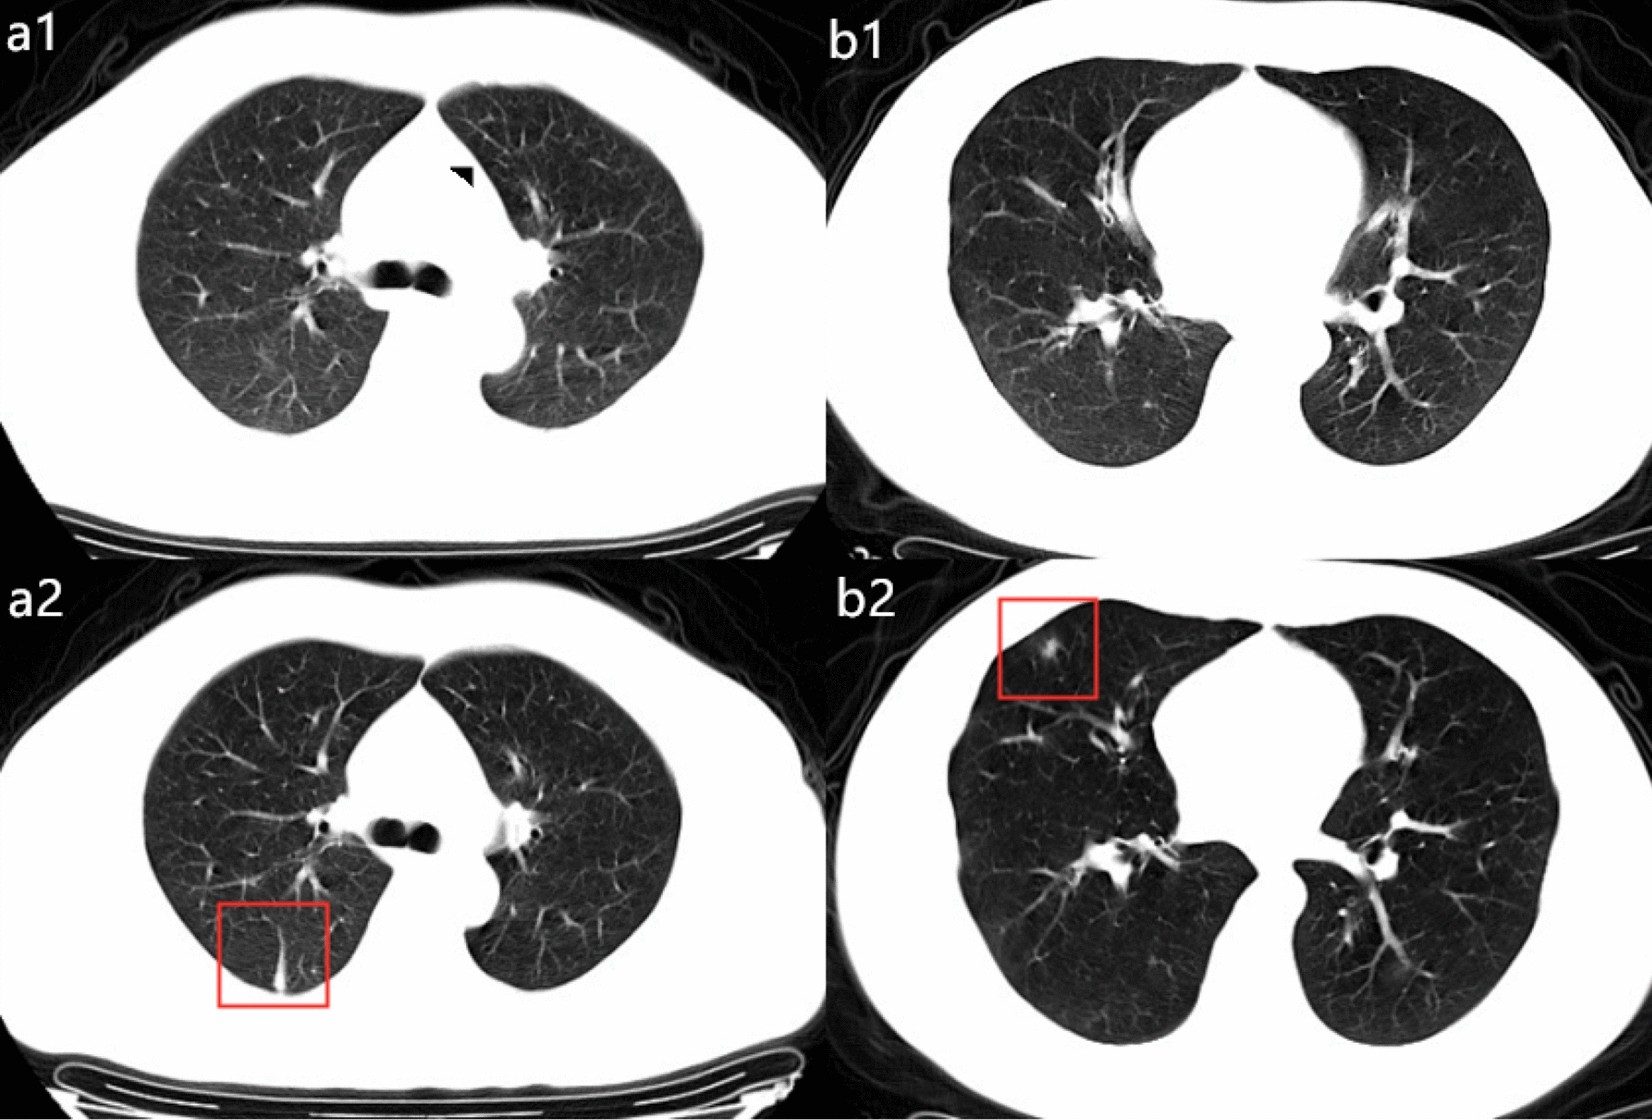

Figure 3

Examples of patients with admitting diagnosis as non-pneumonia in Group 2. (a1–a2) a 45-year-old man with confirmed with non-pneumonia COVID-19 and had hospitalization days of 16. Patients had fever at onset of disease, but normal CT images at the beginning of the admission (a1), at 4th day on admission, the follow-up CT images demonstrated inflammatory appearance as linear shadowing (a2). (b1–b2) a 31-year-old man diagnosed as non-pneumonia with COVID-19 who had cough at onset but normal CT images (b1). Total hospitalization time was 18 days. After 4 days admission, an irregular consolidate nodule can be seen in the right middle lobe from the follow-up CT images (b2).